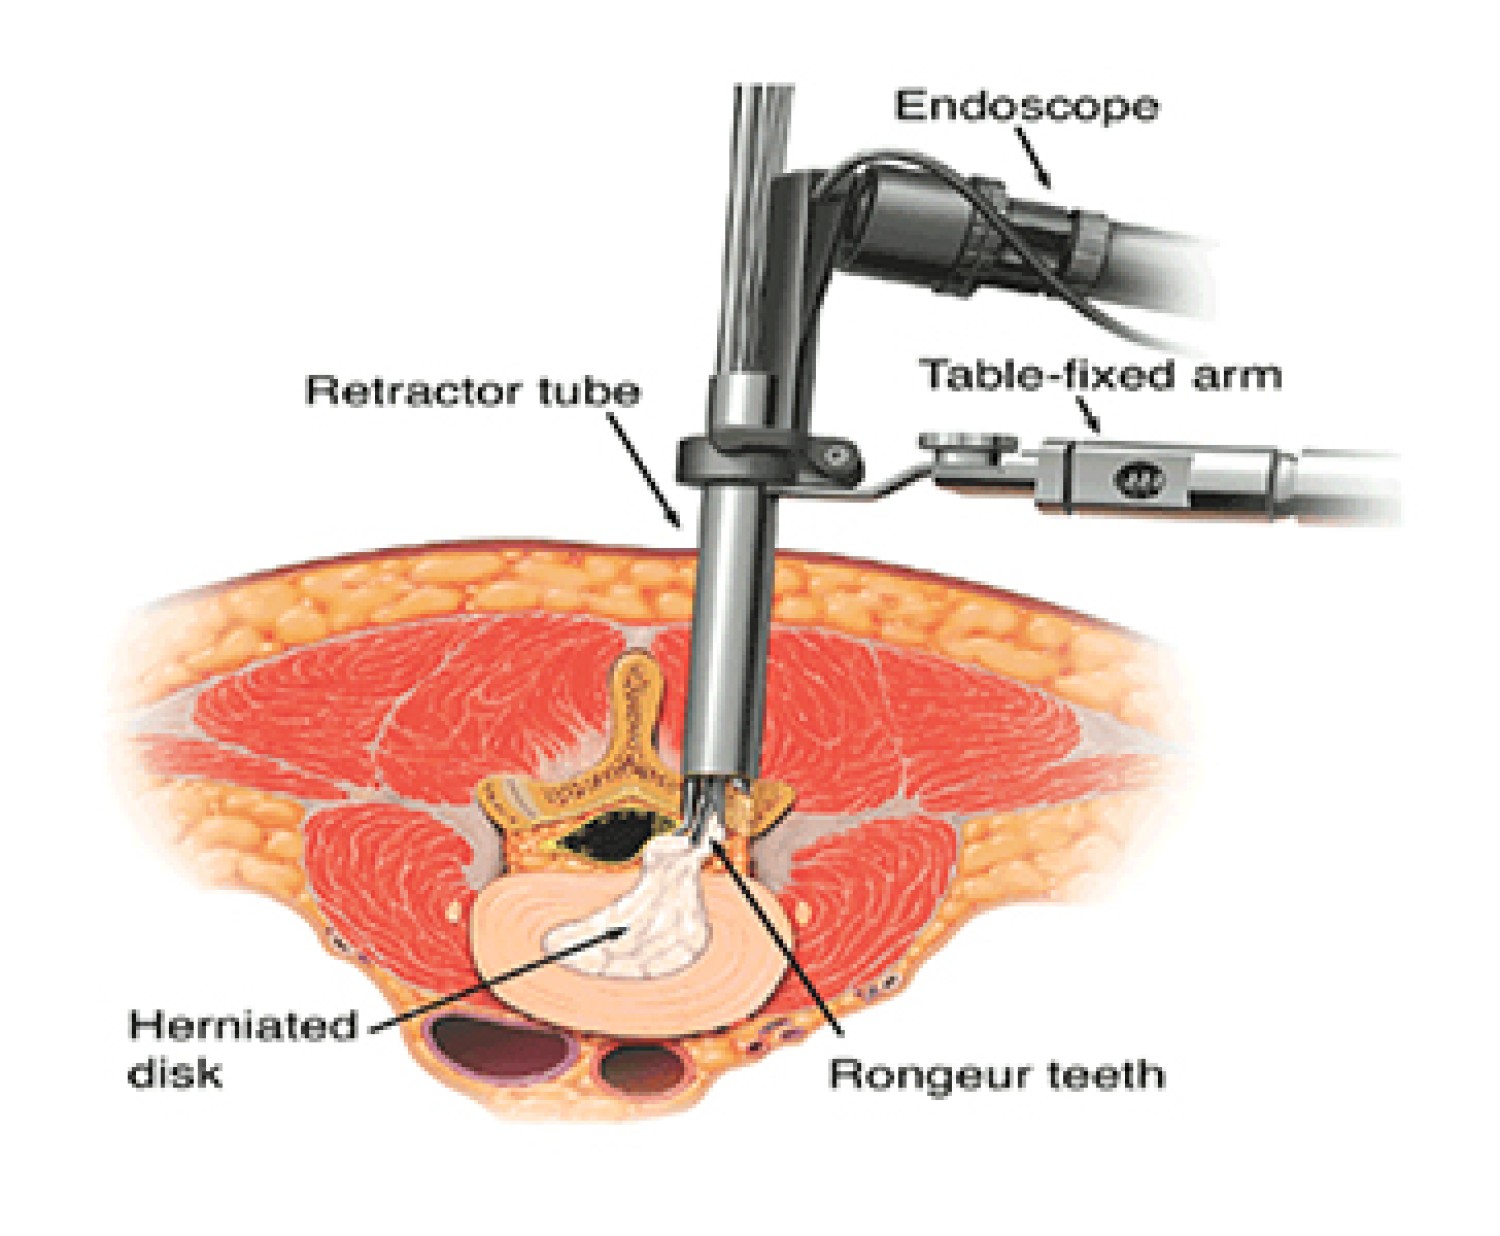

Minimally Invasive Spine Surgery